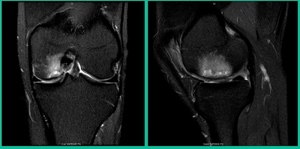

This is an 11-year-old. Left knee lateral knee pain. Effusions, the same type of classic findings (Figure 3)

You look at this one, you say, “what are you going to see when you get in there?” This is one when you get in there, you say, I’m not even sure I’m in the right knee because you almost don’t see it. That happens in patients who were painful, but they don’t look macroscopically unstable. Pediatric orthopedic surgeons tend to drill these. These are the ones that I see as failures. I think when you’re talking about something that’s mechanically unstable, it’s hard to understand why drilling would actually make it work without fixation. Even if it’s microscopically unstable.